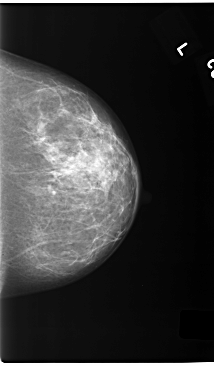

C_0168_1.LEFT_CC

LEFT_CC LINES 5848 PIXELS_PER_LINE 3416 BITS_PER_PIXEL 12 RESOLUTION 50 NON_OVERLAY